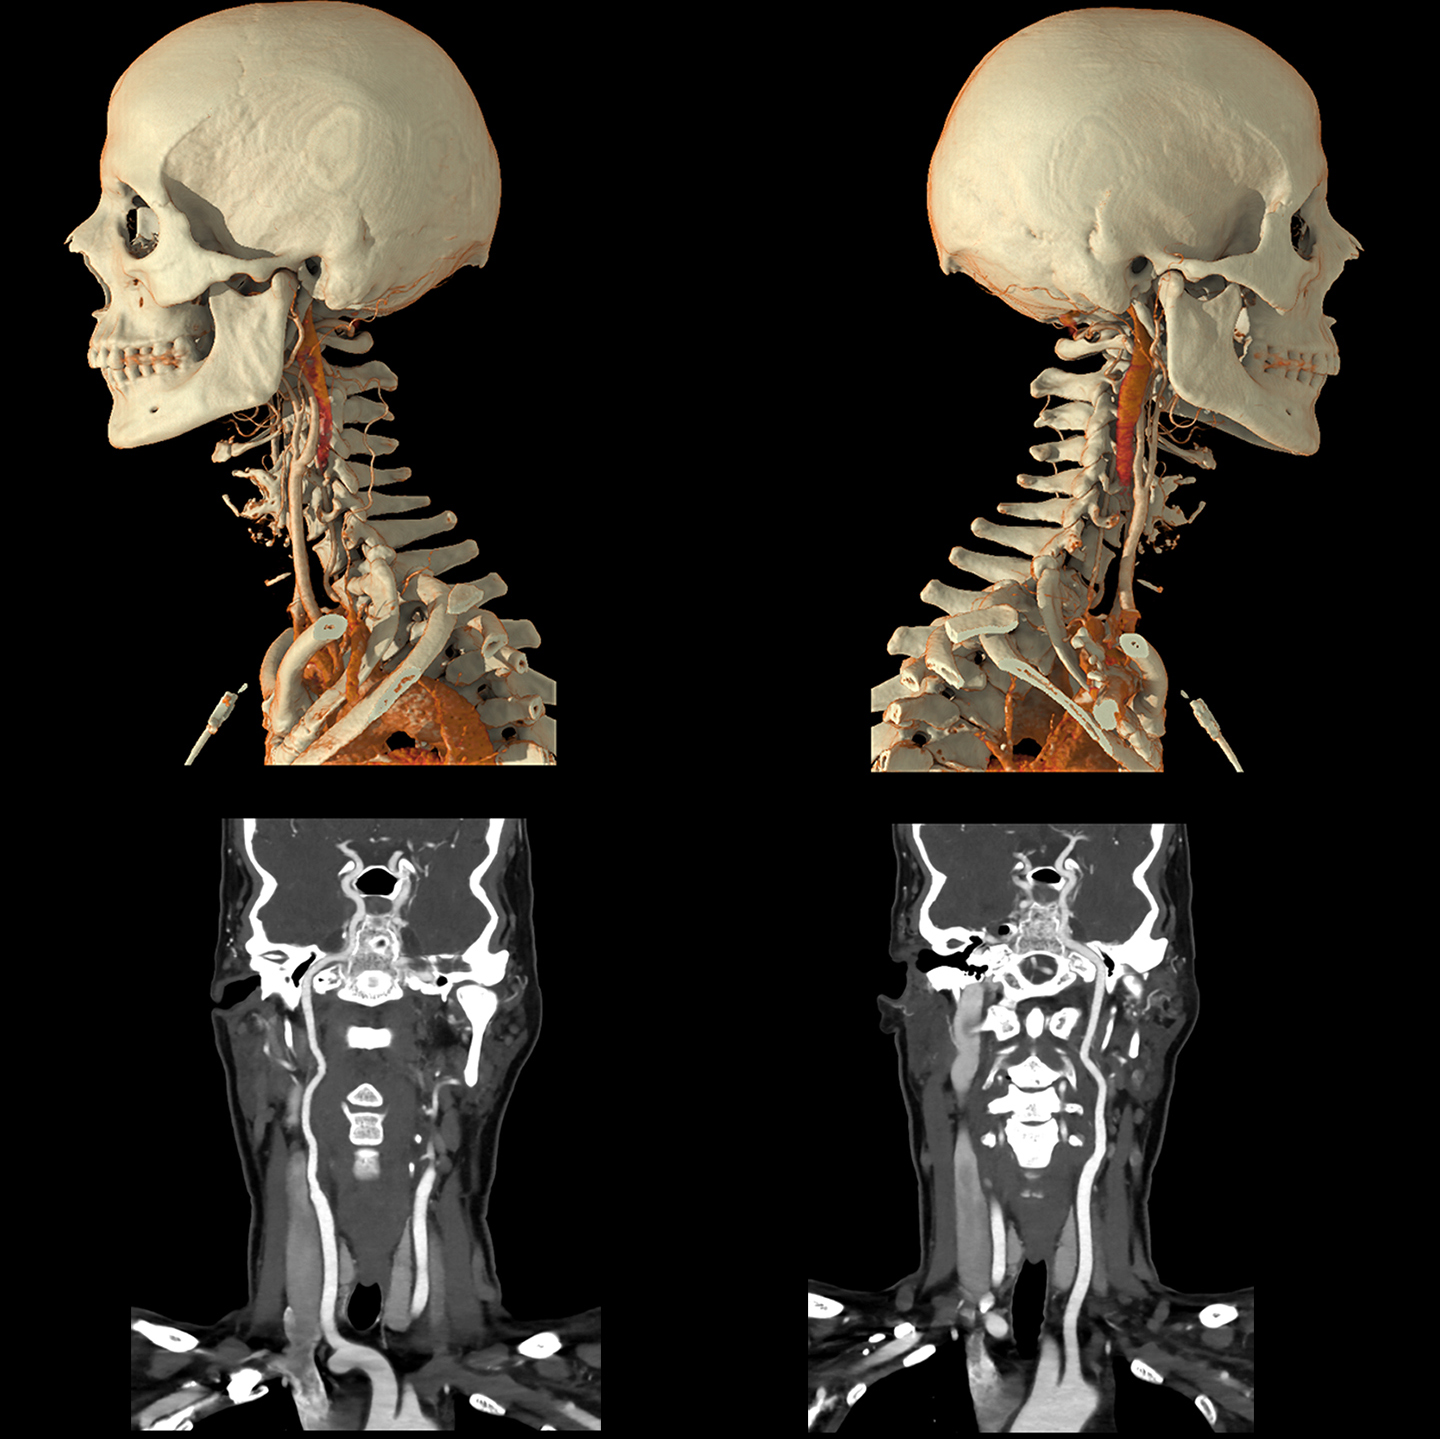

Технология реконструкции сверхвысокого разрешения для компьютерной томографии на основе глубокого обучения

Precise IQ Engine (PIQE)

PIQE обеспечивает улучшенное пространственное разрешение и снижение шума на 45%* для улучшения визуализации в стенте с четким изображением просвета сосуда для оценки неоинтимальной гиперплазии и рестеноза в стенте. Высокая контрастность по сравнению с шумовыми свойствами исследований PIQE также обеспечивает лучшую оценку в сильно кальцифицированных коронарных артериях без потери низкоконтрастной обнаруживаемости* — и эти преимущества обеспечиваются без дополнительной дозы.

Надежные для всех пациентов исследования One beat CTA с PIQE предлагают:

- более четкие анатомические детали,

- уменьшение засветов кальция,

- без дополнительной дозы,

- изофазная однородность.

*по сравнению с AIDR 3D